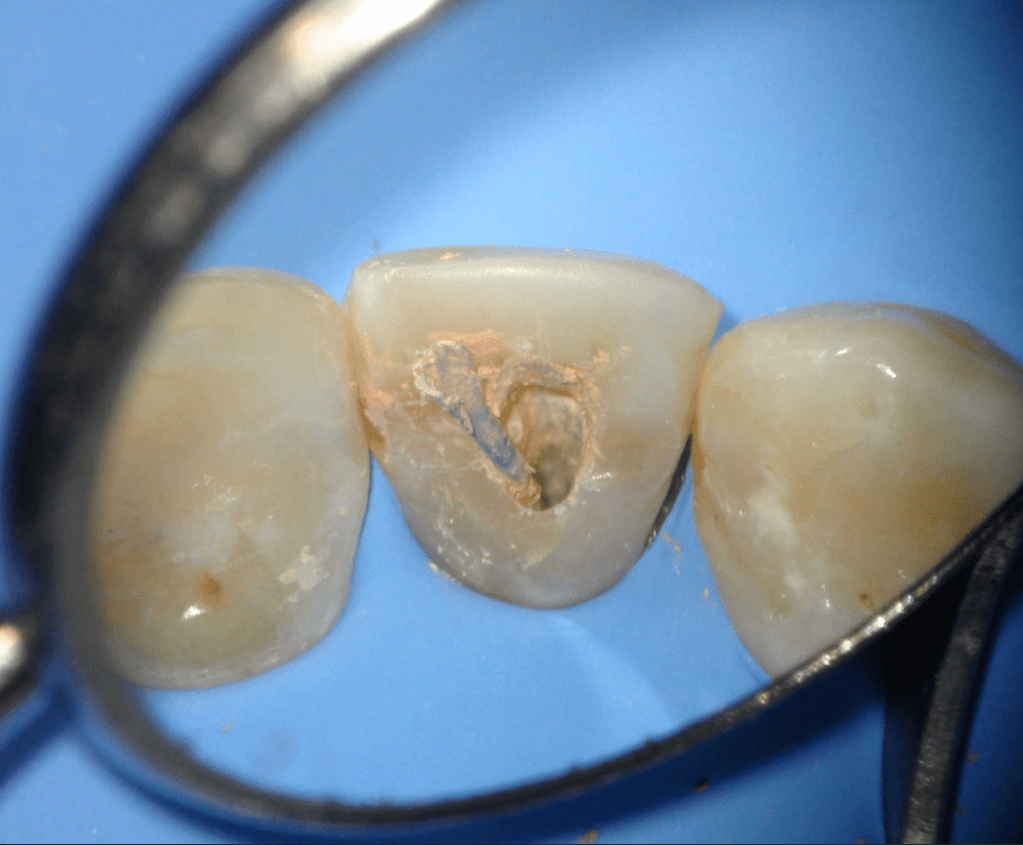

Fisura, remoción amalgama para explorar